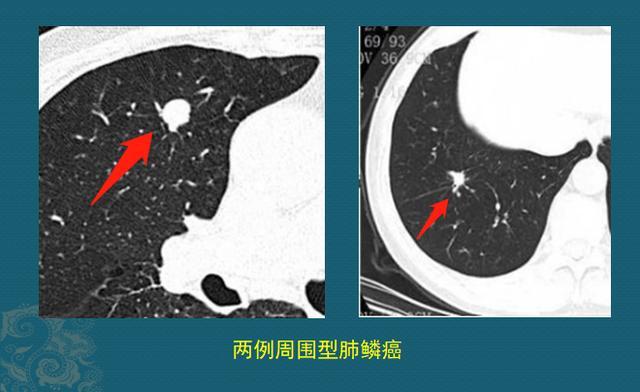

2.早期周围型肺鳞癌

这种的多表现为肺结节,具备恶性征象的大家都会看,比如有分叶、毛刺、偏心小空洞、小气管截断等,我们介绍两个不典型的:光滑小结节、硬结灶

少部分早期周围型肺鳞癌可以很光滑圆润,没有明显恶性征象,貌似良性肺结节;还有些貌似良性的肺纤维灶,定期复查是很好的鉴别方法:

图片病例来自浙江舟山曹捍波教授

这两位老爷子都是周围型肺鳞癌,左边这个很光滑,右边这个像硬结灶,随访观察都缓慢长大,排除了陈旧性良性病灶,果断手术切除,治愈了。这么小的肿瘤,早期生长速度都很慢,随访观察不会耽误治疗